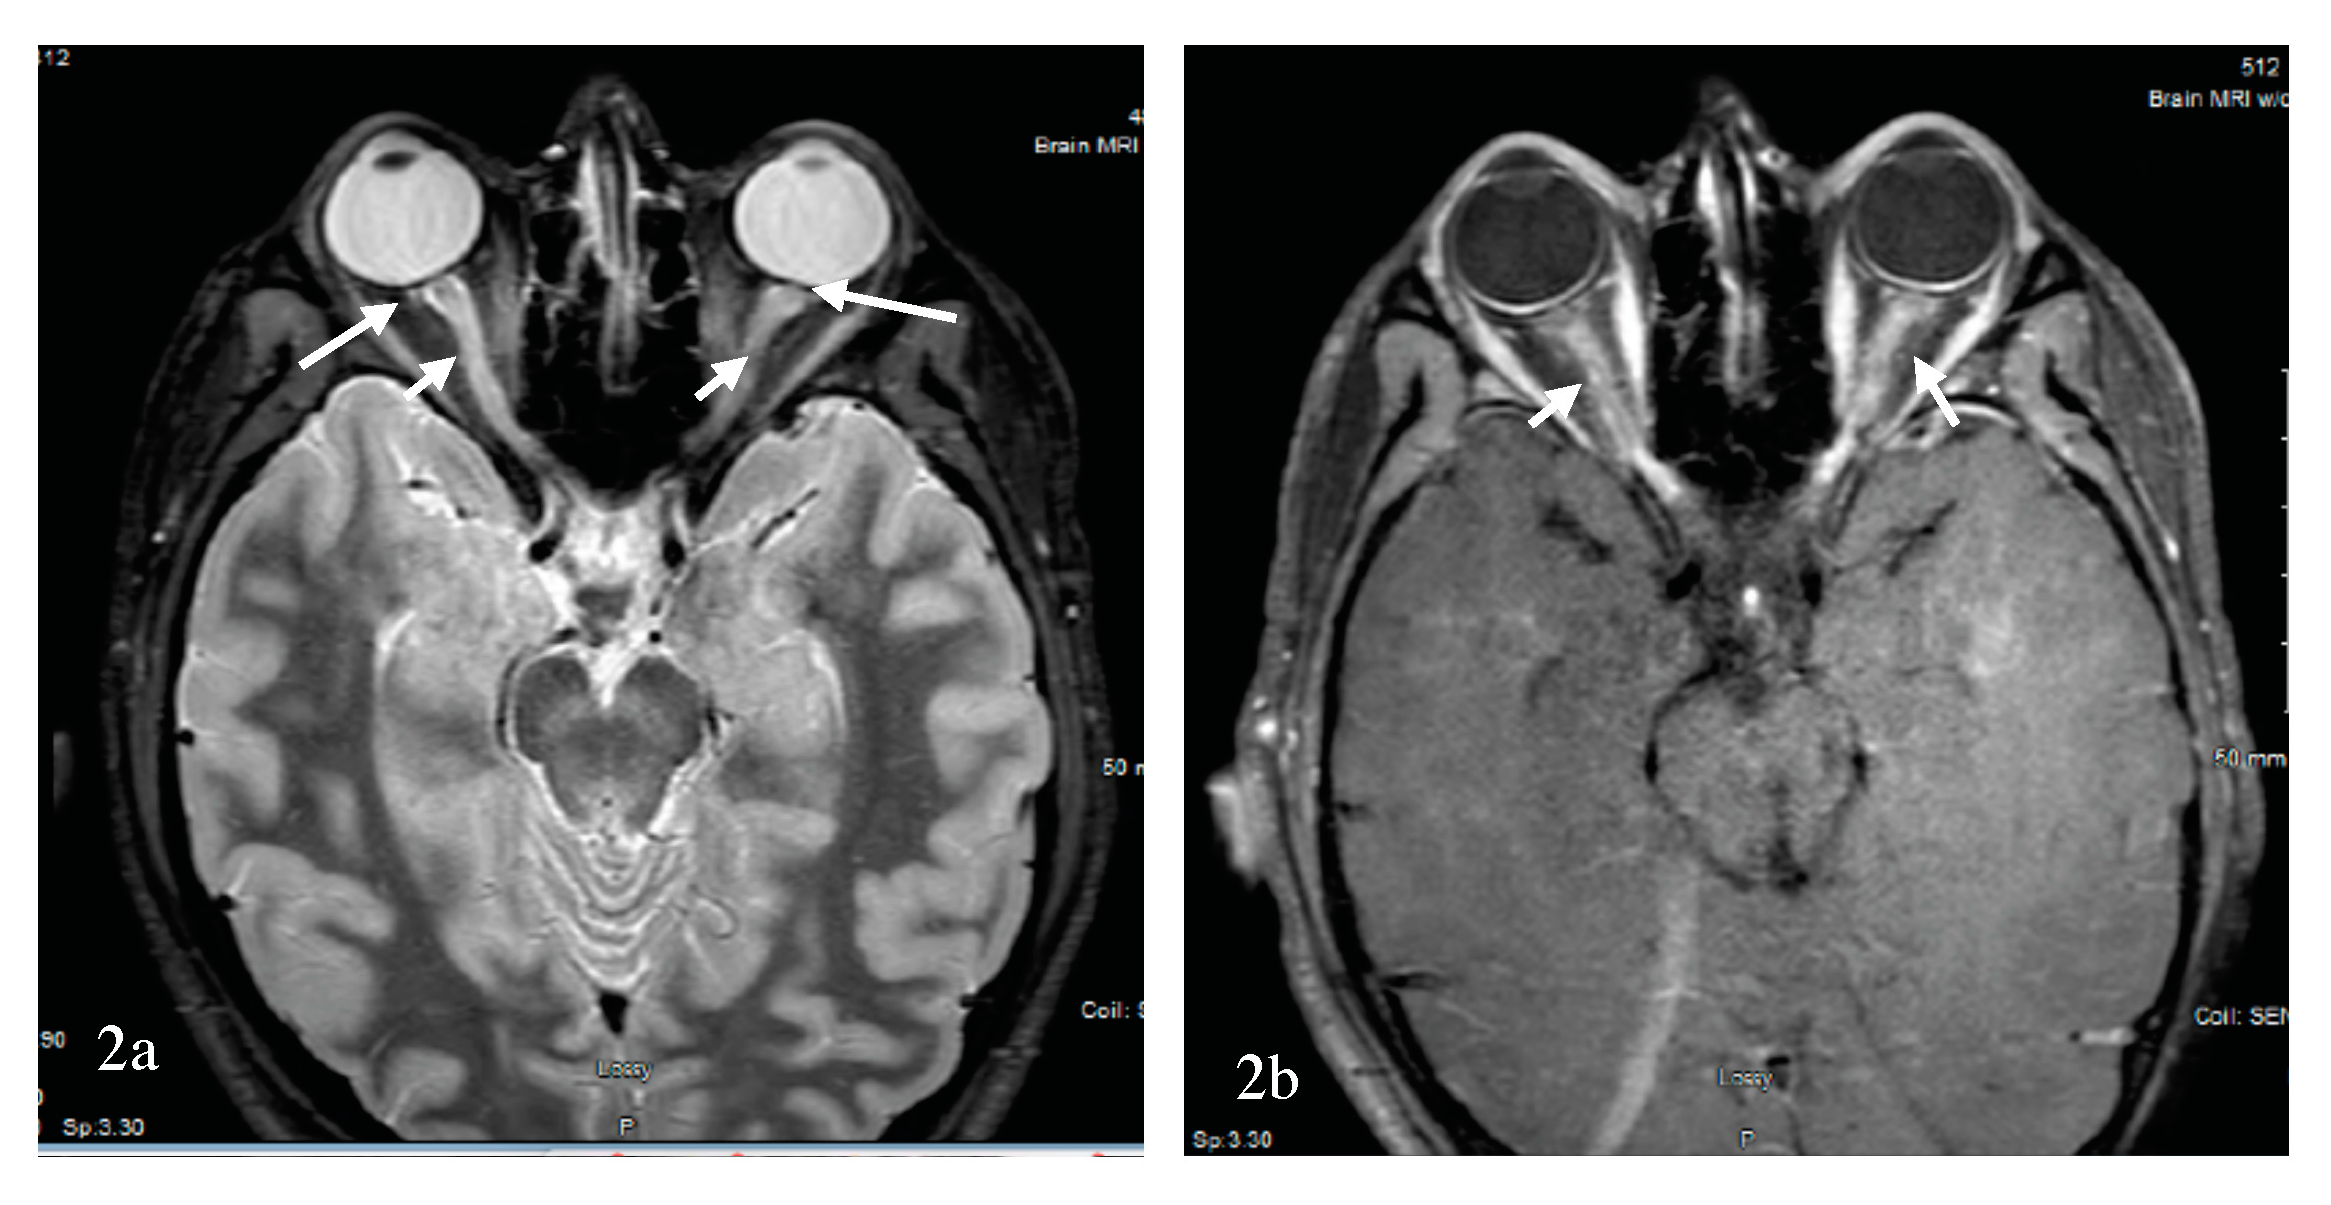

- Buch, D.; Savatovsky, J.; Gout, O.; Vignal, C.; Deschamps, R. Combined brain and anterior visual pathways’ MRIs assist in early identification of neuromyelitis optica spectrum disorder at onset of optic neuritis. Acta Neurol. Belg. 2017, 117, 67–74. [Google Scholar] [CrossRef] [PubMed]

- Storoni, M.; Davagnanam, I.; Radon, M.; Siddiqui, A.; Plant, G.T. Distinguishing optic neuritis in neuromyelitis optica spectrum disease from multiple sclerosis: A novel magnetic resonance imaging scoring system. J. Neuroophthalmol. 2013, 33, 123–127. [Google Scholar] [CrossRef] [PubMed]

- Ramanathan, S.; Prelog, K.; Barnes, E.H.; Tantsis, E.M.; Reddel, S.W.; Henderson, A.P.; Vucic, S.; Gorman, M.P.; Benson, L.A.; Alper, G.; et al. Radiological differentiation of optic neuritis with myelin oligodendrocyte glycoprotein antibodies, aquaporin-4 antibodies, and multiple sclerosis. Mult. Scler. 2016, 22, 470–482. [Google Scholar] [CrossRef] [PubMed]